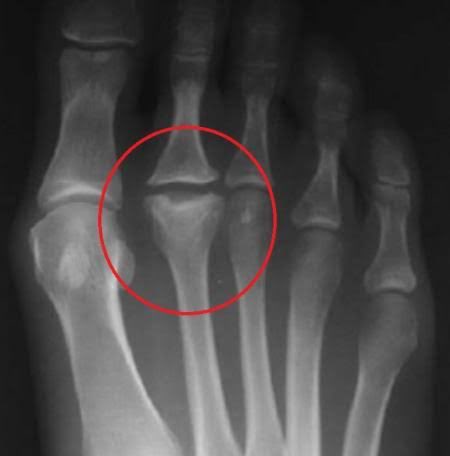

٣-القدم الجوفاء "ذات القوس العالي":

وجود قدم بقوس عالي "عكس المسطحة" يسبب خلل في توزيع الوزن على القدم.

حيث يصبح الوزن أثقل على منطقة الكعب و مشط القدم كما هو موضح بالصورة 👇🏼يلاحظ وجود تكلسات على المشط مما يدل على وجود وزن زائد عليها